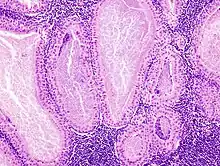

The appearance of this tumor under the microscope is unique. There are cystic spaces surrounded by two uniform rows of epithelial cells with centrally placed pyknotic nuclei. The cystic spaces have epithelium referred to as papillary infoldings that protrude into them. Additionally, the epithelium has lymphoid stroma with germinal center formation.

Low magnification micrograph of a Warthin tumor arising from the parotid gland.

Histopathology of Warthin tumor in the parotid gland. H&E stain. (Fig 1)